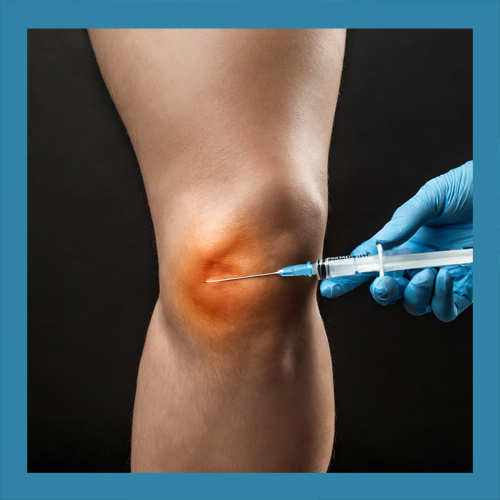

• 주사 치료: 손상된 연골 재생을 돕는다

주사 치료는 반월상 연골 파열 치료에서 점점 더 주목받고 있는 방법입니다. 히알루론산 주사나 PRP(자가혈소판농축혈장) 주사는 관절 윤활을 개선하고 연골의 재생을 촉진하는 데 도움을 줍니다. 이러한 치료는 비교적 간단하며, 회복 기간이 짧다는 장점이 있습니다. 그러나 효과는 환자의 상태와 손상의 정도에 따라 달라질 수 있습니다.